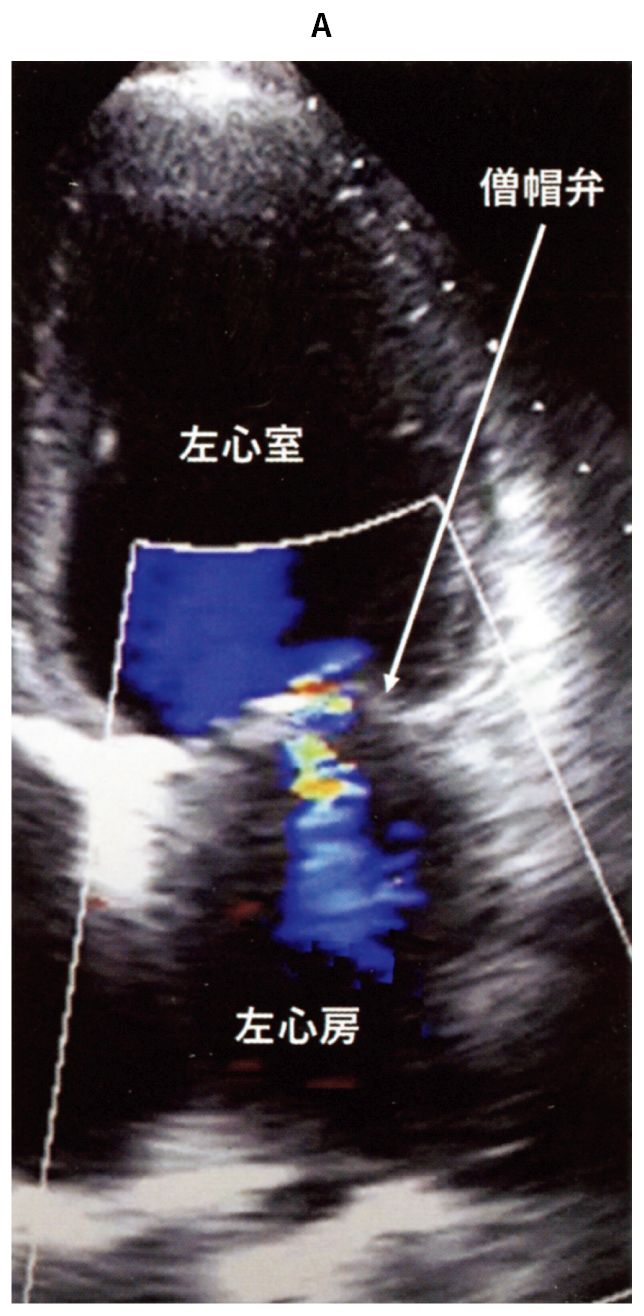

63歳の男性。健診で心雑音を指摘され来院した。ジョギングの運動習慣があるが,息切れなどの自覚症状はない。身長166cm,体重62kg。体温36.2℃。脈拍68/分,整。血圧114/80mmHg,左右差なし。呼吸数16/分。SpO2 97%(room air)。頸静脈の怒張を認めない。心音は心尖部を最強点とするLevine 2/6の汎〈全〉収縮期雑音を聴取する。呼吸音に異常は認めない。下腿浮腫を認めない。血液所見:赤血球445万,Hb 14.7g/dL,Ht 41%,白血球6,100,血小板22万。血液生化学所見:総蛋白6.9g/dL,AST 25U/L,ALT 24U/L,LD 164U/L(基準124~222),CK 110U/L(基準59~248),尿素窒素21mg/dL,クレアチニン1.1mg/dL,eGFR 60mL/分/1.73m2,血糖104mg/dL,Na 136mEq/L,K 3.9mEq/L,Cl 110mEq/L,BNP 15pg/mL(基準18.4以下)。CRP 0.2mg/dL。胸部エックス線写真に異常を認めない。心エコー検査で左室駆出率68%,左室の拡大は認めない。カラードプラ心エコー図の心尖部二腔断面像(A)と12誘導心電図(B)とを下に示す。